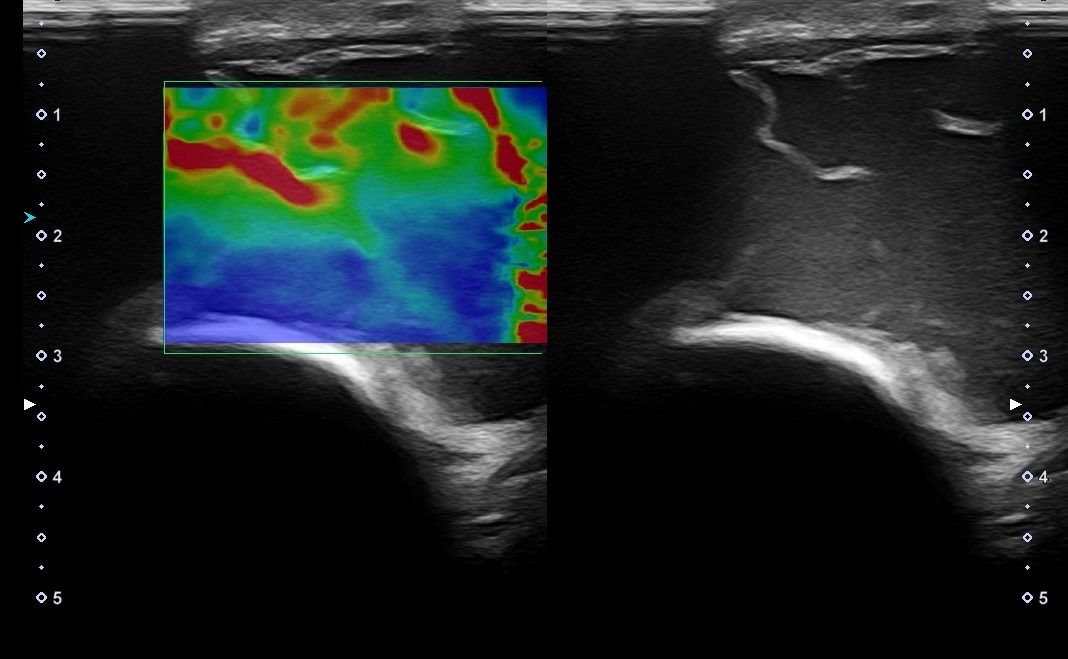

Elbow Ultrasound provides comprehensive imaging of various structures in the region, allowing the identification of pathologic conditions in the joint, bursae, tendons, ligaments, nerves, and soft tissues of the elbow.

Dynamic Testing: Ultrasound is inherently a dynamic imaging method, meaning that the examination and diagnosis can occur during movement. This capability is particularly important for Elbow Ultrasound, allowing a comprehensive examination of the area in various positions and movement points.